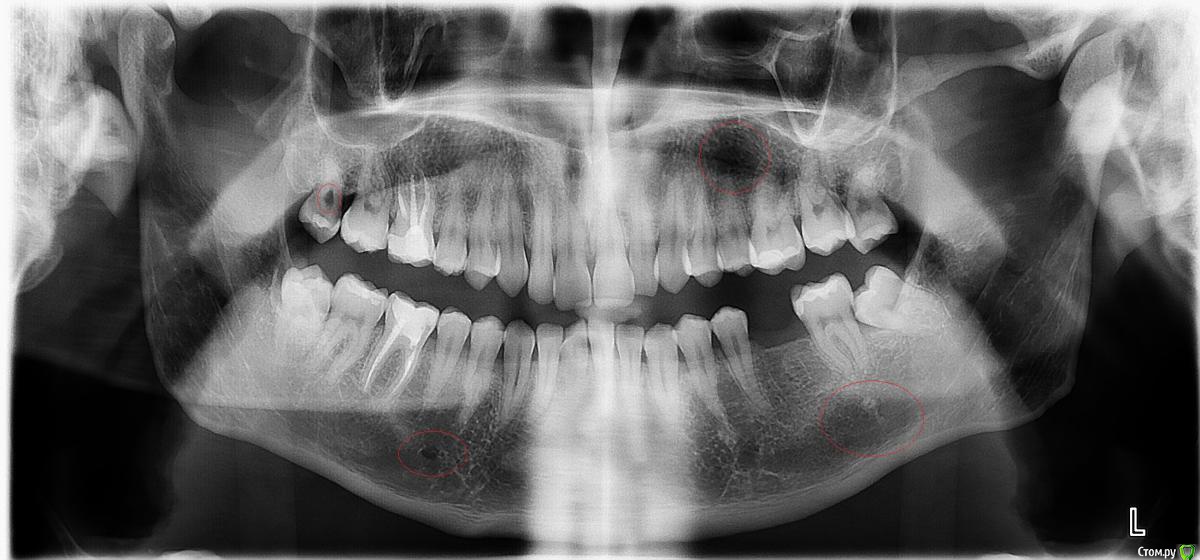

Vtelenkov Опубликовано 25 ноября, 2015 Поделиться Опубликовано 25 ноября, 2015 (изменено) Добрый день. Проконсультируйте пожалуйста. Ситуация следующая: 6 слева удалил год назад с прицелом на имплантацию, 8 слева планировал удалить еще весной, но всякие хвори постоянно мешали, а недавно и совсем огорчили - онкология. Примерно через две недели ожидаю начала ХТ и соответственно серьезные вмешательства недопустимы, если нет показаний по срочности. Но, существуют след. проблемы, а именно 6-ки справа очень чувствительны к холодному, горячему, сладкому и пр пр. Между 7-кой и 8-кой слева постоянно что-то воспаляется, спасаюсь шалфеем и хлоргексидином. А так же отмеченные места на снимке. Стоматолог, на очном приеме, не нашел чего-то криминального,требующего экстренного вмешательства, но хочется услышать второе мнение. Снимок большого размера - https://i.imgur.com/mbXGFcQ.jpg Заранее спасибо. Изменено 25 ноября, 2015 пользователем Vtelenkov Ссылка на комментарий

Гарриевич Опубликовано 25 ноября, 2015 Поделиться Опубликовано 25 ноября, 2015 то, что Вы отметили это ментальное отверстие (левый кружочек) и просто наложение кости на снимке (кружочек правый)слева 8ка упирается в 7ку с образованием десневого кармана и возможным кариесом 7го зубаудалить 8ку советовал бы на днях, до начала ХТ все заживет Ссылка на комментарий